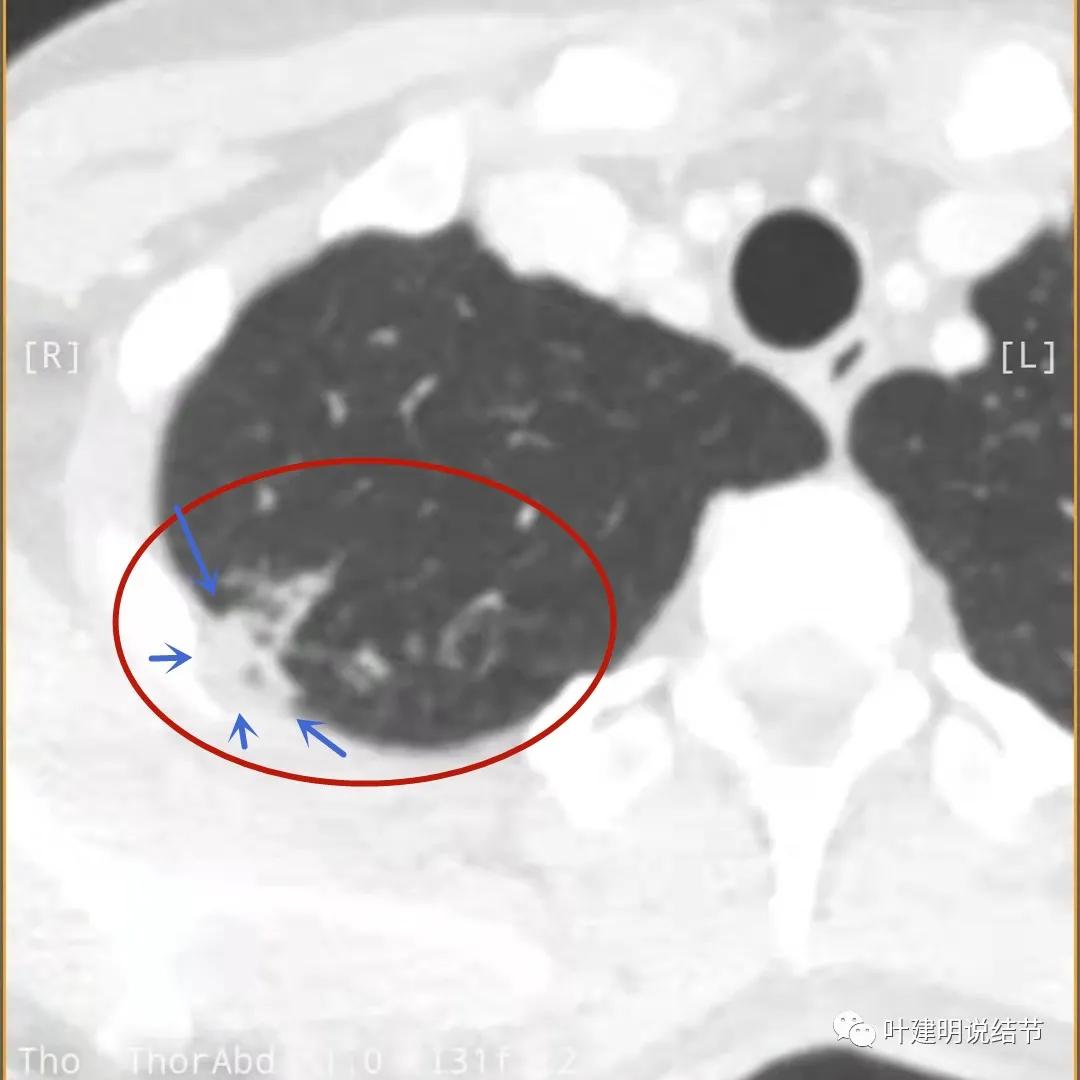

上面是她提供的病史资料,其中最重要的是PPD强阳性!其他主要看影像,我们先来看她2020年7月份的平扫片子(由于片子较多,详细展示是为了同道分析,我在影像特征描述上将只选取部分加以说明):

右肺尖偏实性结节(粉色箭头),邻近胸胸膜明显增厚不平,且广基附在胸壁上(蓝色箭头)

有卫星病灶(绿色箭头)

胸壁侧病灶较厚,模糊(蓝色箭头),仍见卫星灶(绿色箭头)

主病灶出现,粉色箭头示病灶密度较高,边上有磨玻璃影,甚淡(砖色箭头)

病灶有空洞(黄色箭头),主病灶边上见条索状高密度影(细红色箭头),邻近胸膜有粘连(蓝色箭头)

邻近胸膜明显增厚,且广基底,主病灶前方有小片磨玻璃影

主病灶与胸膜间基本相连,模糊清(蓝色箭头),主病灶壁厚薄欠均,边上有高密度条索状(桔色箭头)

主病灶不见了的层面,仍有边上高密度条索状的影像,邻近胸膜仍有异常(蓝色箭头)

影像初印象:右上病灶散在,不致密,密度偏高,磨玻璃影不是平时典型恶性的磨玻璃瘤肺边界清楚或含毛刺征的征象,更符合炎性病变,且邻近胸膜广基的异常增厚。